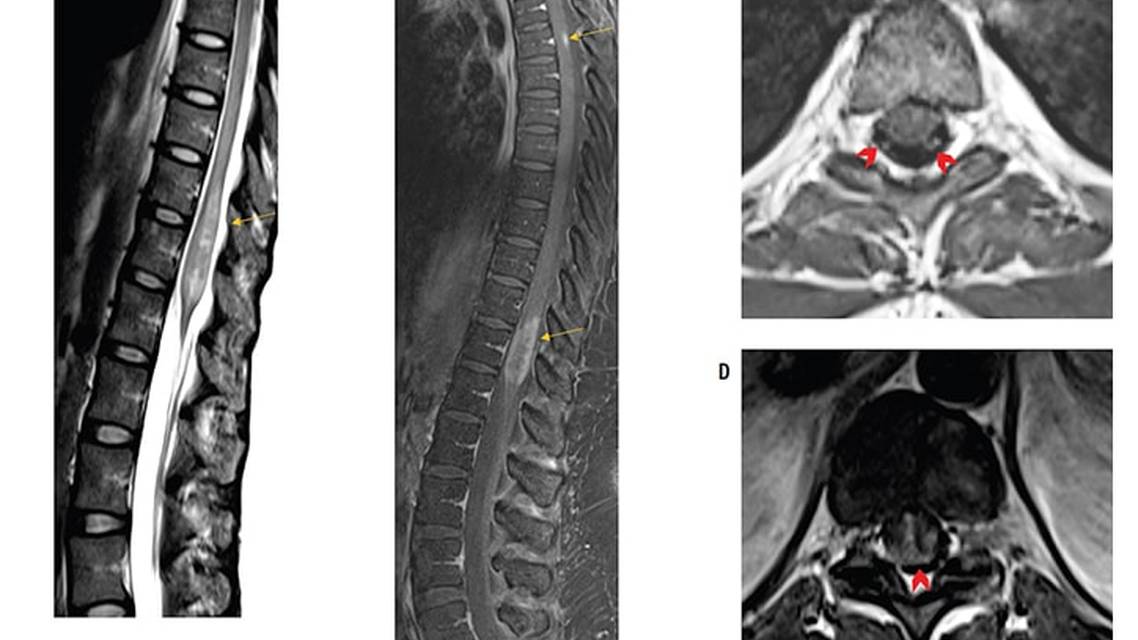

MRI scans of the cervical, thoracic, and lumbar spine with and without contrast revealed an enhancing lesion extending from the distal thoracic cord to the conus medullaris, consistent with longitudinally extensive transverse myelitis (LETM; Figure, A and B). Additional enhancing lesions were present along the dorsal surface of the spinal cord at the T4 level (Figure, B), and at the distal aspect of the thecal sac (Figure, A). There was also faint enhancement of some of the lower thoracic dorsal roots (Figure, C). On the cross-section of the lower thoracic lesion, the trident sign could be readily appreciated (Figure, D). Brain MRI with and without contrast was unremarkable.

Despite the low-positive AQP4-IgG result, certain aspects of the presentation were atypical for NMOSD.1 The presence of CSF-restricted oligoclonal bands is seen in a minority of NMOSD cases.2 Root involvement, as seen in MA (Figure, C), is unusual but has been reported.3,4 Mildly elevated CSF CD4:CD8 and lymphocytic pleocytosis could be suggestive of, but not specific for, neurosarcoidosis.5,6 A history of dermatologic eruptions could represent an unrelated condition, but could also be a manifestation of a systemic inflammatory process, such as sarcoidosis. In addition, postgadolinium T1-weighted axial MRI revealed a pattern of central and dorsal-subpial enhancement, referred to as the trident sign, which has been reported in sarcoid myelitis but not in AQP4-IgG–positive NMOSD (Figure, D).7

Sarcoidosis is a systemic immune-mediated disorder characterized by the formation of noncaseating granulomas in affected tissues.12 A total of 5% to 10% of people with sarcoidosis present with a neurologic syndrome, with myelopathy accounting for 5% to 25% of these cases.6,13 Diagnosis of neurosarcoidosis is notoriously challenging because of the heterogeneity of clinical presentation. When the spinal cord is involved, enhancement along the cord’s dorsal surface is common, and cauda equina involvement with enhancement along nerve roots may be seen, both of which were present in our case (Figure, A and B).3,11 Spinal leptomeninges can also be affected.11 The trident sign is a radiologic finding proposed to have high specificity for the diagnosis of neurosarcoidosis.7 Several case reports have specifically cited its usefulness for differentiating neurosarcoidosis from NMOSD in cases of atypical imaging findings or false-positive AQP4-IgG antibodies.7,14,15 The trident sign was visualized on the thoracic MRI in MA, whose laboratory investigations and response to treatment, as well as the absence of extraneural involvement or lymphadenopathy on whole-body positron emission tomography–CT scanning, ultimately supported a diagnosis of NMOSD (Figure, C). A recent case report also documented the trident sign in an individual with spinal cord lymphoma, bringing into question the specificity of this radiologic finding for neurosarcoidosis.16 This sign needs to be assessed systematically in people with or without neurosarcoidosis to clarify the sensitivity and specificity of this finding, and to help clarify its immunopathologic basis.